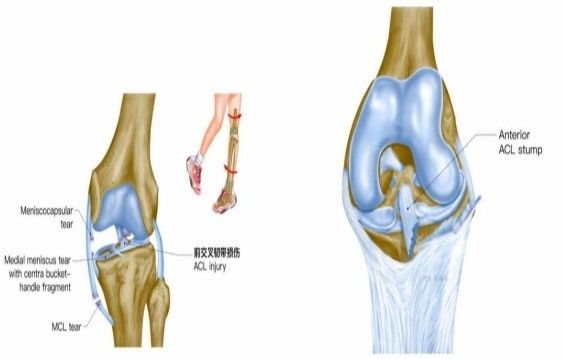

欧洲杯预选赛小组赛中,被誉为“欧洲金童”年仅20岁的运动员加维,右膝交叉韧带撕裂,面临赛季报销+无缘欧洲杯的痛苦。在运动损伤中,“韧带撕裂”是一个出现频率非常高的词,无论是运动员或者是普通人,在生活和运动中都可能会遭遇“韧带撕裂。”

我院骨科三病区近期收治了4名膝关节交叉韧带损伤患者。25岁的齐先生,因打篮球时不慎扭伤左膝,致右膝肿痛,遂来我院治疗;30岁赵先生酷爱足球,扭伤右膝关节来我院就诊;50岁的张先生、42岁刘先生因骑车滑倒摔伤、膝关节肿痛不适、活动受限,收治入院。骨科三病区李鹏主任团队详细查体以及完善影像学检查后进行诊断:几位患者共同诊断均有“前交叉韧带损伤”,不同程度合并有“半月板损伤”、“股骨软骨损伤”、“内侧副韧带断裂”。

致伤机制

单纯前交叉韧带损伤可发生于非负重条件下膝强力过伸时(如用力踢时未遇到抵抗),或小腿固定、暴力使股骨向后时。单纯前交叉韧带损伤少见,多合并胫侧副韧带、半月板的损伤,此三结构的复合伤在膝部韧带损伤中最为常见(占52%)。损伤多发生于韧带中部(占 72%),少数发生于股骨附着点撕脱骨折 (18%)或胫骨附着点撕脱骨折(4%)。损伤后关节内出血、疼痛、活动受限、前抽屉试验阳性。